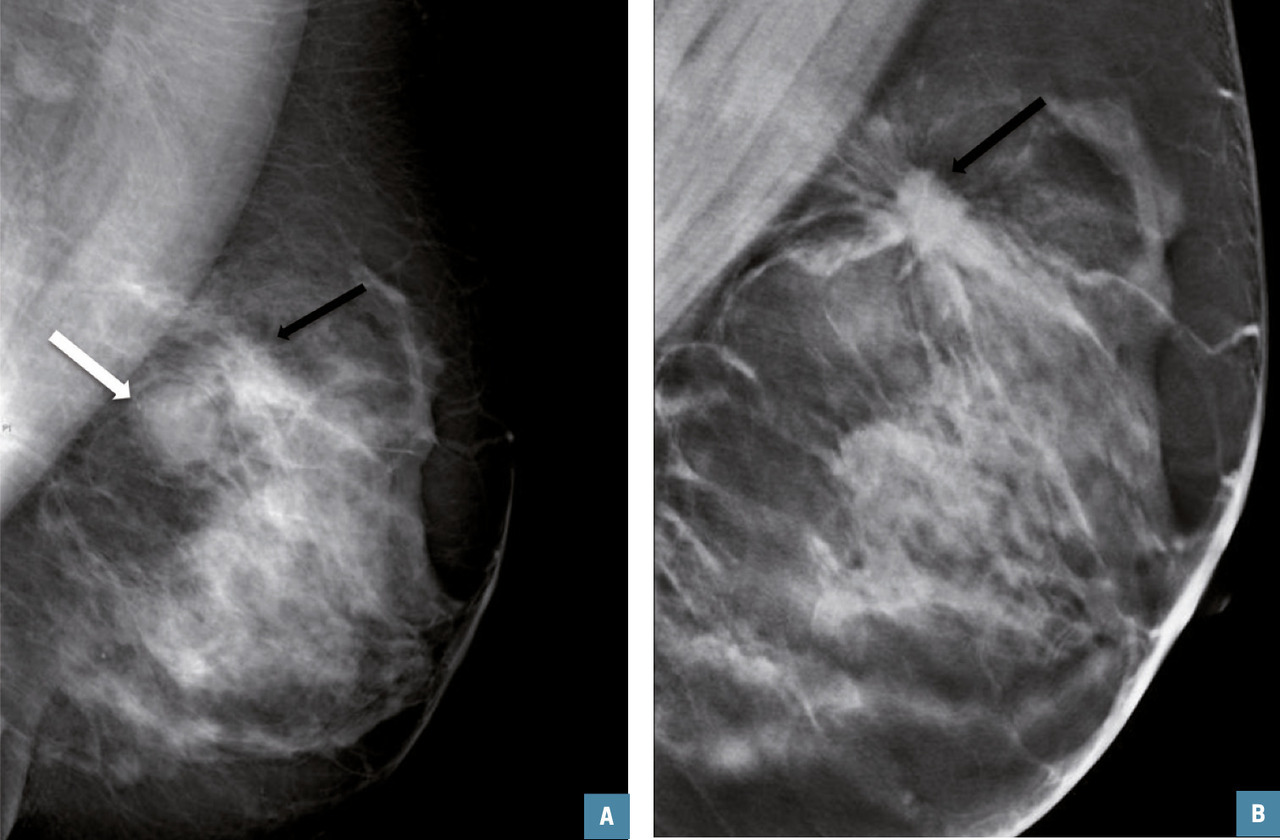

De plus, si cette technique a peu d’intérêt dans l’identification et la caractérisation d’un foyer de microcalcifications, elle permet de mieux évaluer les contours d’une lésion potentielle et d’individualiser une distorsion architecturale. En revanche, elle fournit peu d’arguments spécifiques quant au caractère malin (carcinome canalaire invasif, tubuleux) ou bénin (cicatrice radiaire et surtout postopératoire) de cette dernière.

Dans les asymétries de densité, on peut identifier des signes associés de distorsion architecturale (spicules épais et courts sans centre dense ou alors de petite taille) orientant vers la malignité.